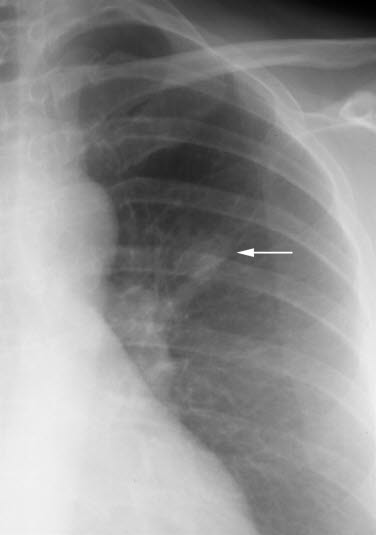

Røntgen-bilde viser en liten og litt uskarpt avgrenset tumor i venstre lunge (pil). Samme tumor som "Lungecancer CT"